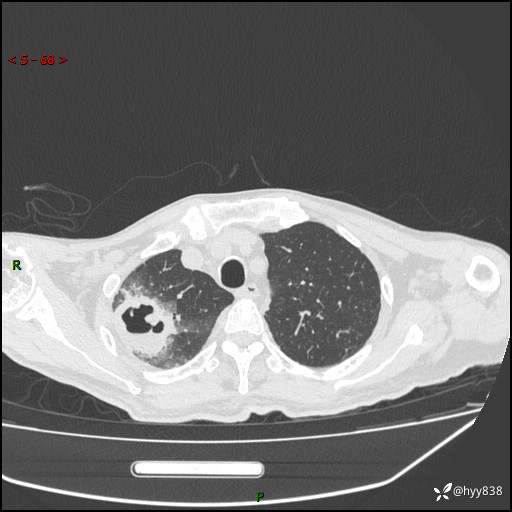

一个月后第二次CT检查(常规抗感染,患者不配合:增强、住院---)